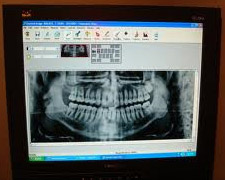

Our office utilizes modern digital x-rays, not film x-rays. This means that a tiny sensor is placed gently in the mouth and the x-ray image 'pops' immediately on the computer screen. Kids are encouraged to make a 'puzzle' on the screen. Kids really get excited as we show them how we can zoom in, enlarge and colorize the pictures! Little does the child know that this method utilizes at least 60% less radiation than the old chemical kind.